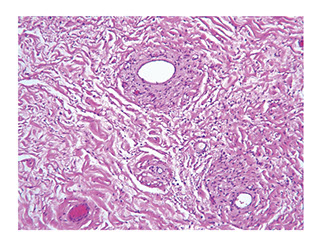

(Aggressive) Angiomyxoma

Rare, infiltrates (slowly) locally in reproductive women, can affect some men(???) and has been found in the vagina

Gross: pedunculated vulvar mass (can kinda look like a penis)

Micro: monotonous, uniformly hypocellular, small spindled and stellate fibroblasts w/o atypia, very rare mits (none are atypical)

- myxoid stroma c collagen and thick-walled vessels (hyaline thickening of adventitia)

- can see RBCs extravasated

- may have chondroid metaplasia

IHC: (+) CD23, vimentin, ER/PR, SMA, HMGA2 (sens  [+ in 1/2] but not spec, also focal)

- negative: CD117, B-catenin, CKs, S100, EMA, caldesmin, MDM2

Genes: HMGA2 gene at 12q15 (sens but not spec)

- also t(12;21)(q15;q21.1) or t(11;12)(q23;q15)

Tx: wide excision, lifelong FU (has very infiltrative borders)

- chemorads not effective bc slow growing

Px: locally aggressive (1/3 recur locally), but does NOT met